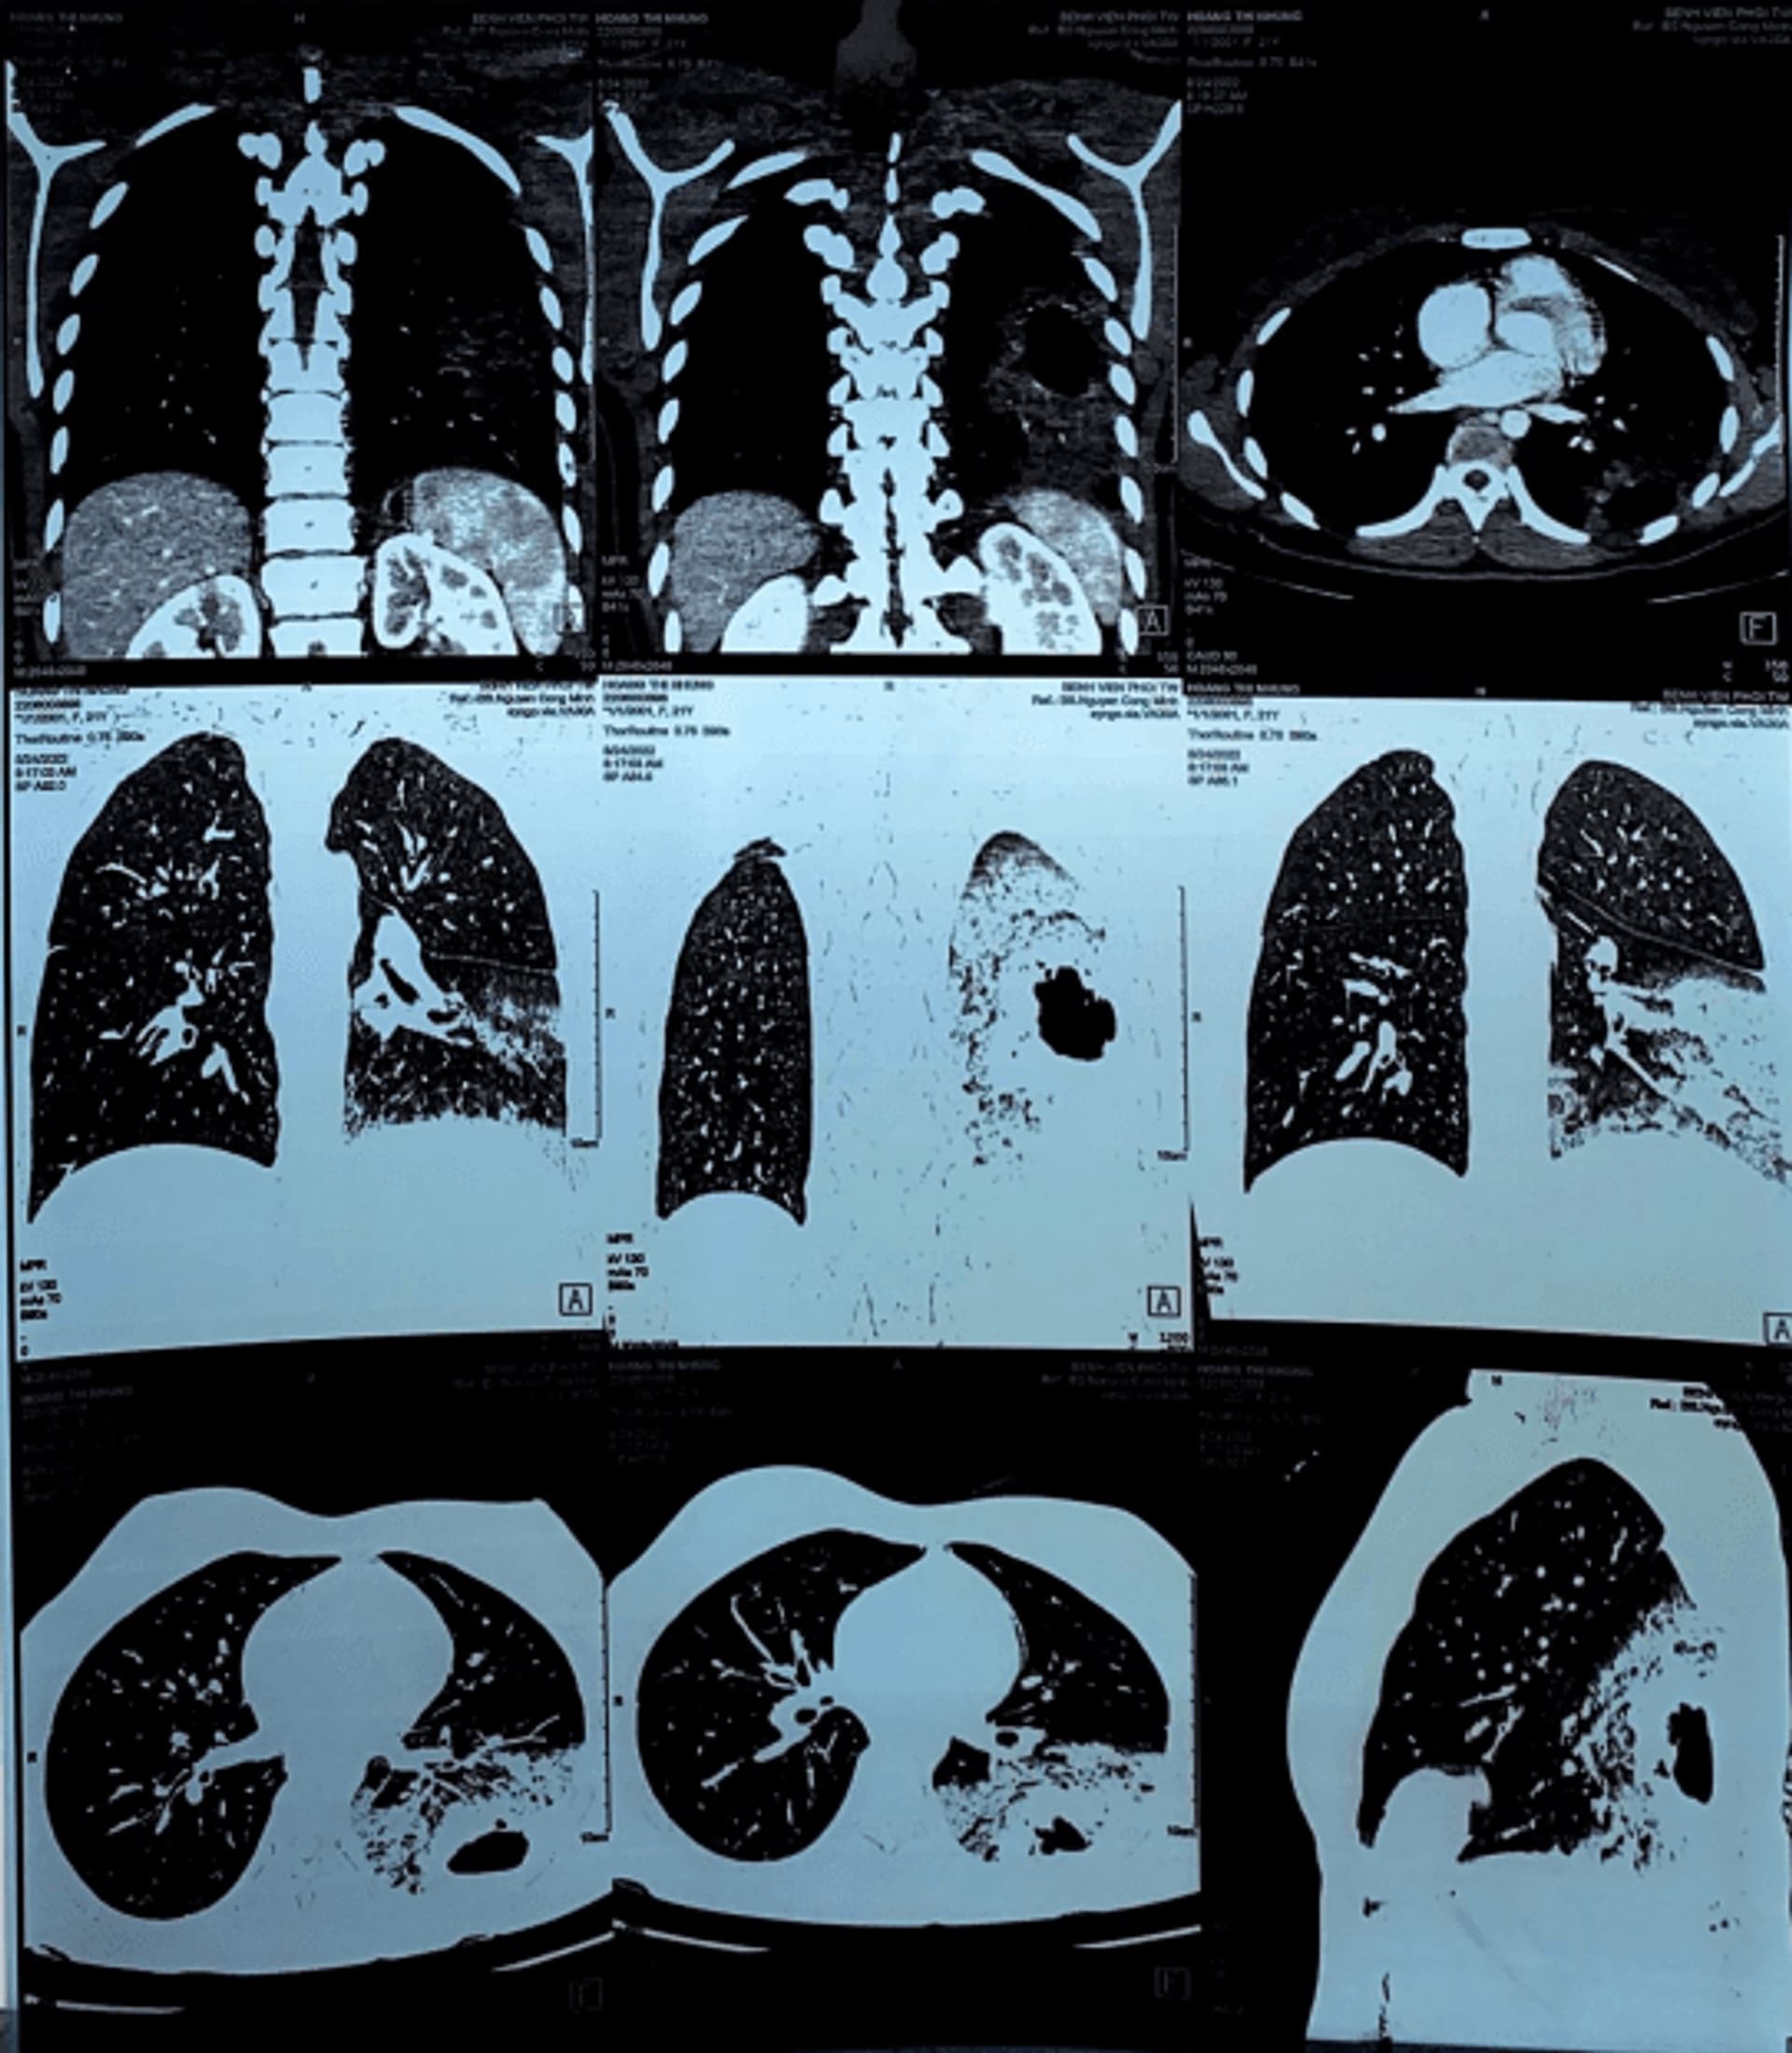

Cuối tháng 8/2022, bệnh nhân H.T.N, 21 tuổi đến khám tại Khoa khám bệnh đa khoa TYC Bệnh viện Phổi Trung Ương với lý do ho khan kéo dài, gầy sút cân, bệnh nhân trẻ tuổi nhưng xanh xao và tinh thần suy sụp. Khi được hỏi, bệnh nhân kể đầu năm 2020 có đi xuất khẩu lao động tại Nhật Bản, sau một năm làm việc tại Nhật Bản, bệnh nhân khám sức khỏe định kỳ phát hiện có tổn thương nhu mô phổi trái, được làm các xét nghiệm tìm nguyên nhân (xét nghiệm máu, đờm, nước tiểu, nội soi phế quản) nhưng không phát hiện ra bệnh. Sau đó bệnh nhân được theo dõi định kỳ và làm lại các xét nghiệm nhiều lần thì bác sỹ tại Nhật Bản nghi ngờ có tế bào lạ trong dịch phế quản phổi và giải thích cho bệnh nhân phải phẫu thuật làm chẩn đoán, lúc này bệnh nhân đã bắt đầu có triệu chứng ho khan kéo dài và gầy sút cân, mệt mỏi. Bệnh nhân và gia đình vô cùng lo lắng nên xin về Việt Nam và lựa chọn khám bệnh tại Bệnh viện Phổi Trung Ương. Tại đây, bệnh nhân được chụp phim CLVT lồng ngực 64 dãy độ phân giải cao cho thấy tổn thương đông đặc tạo hang thùy dưới phổi trái, hình ảnh chưa loại trừ bệnh lý ác tính. Để nhanh chóng có được chẩn đoán chính xác với một trường hợp bệnh nhân trẻ tuổi, bệnh nhân đã được thực hiện gói “chẩn đoán ung thư phổi ngoại trú nhanh” tại Khoa Ung Bướu 2 thuộc Bệnh viện Phổi Trung Ương. Bác sỹ Nguyễn Công Minh, Khoa Ung Bướu 2 cho biết “Sau khi nhận được thông tin bệnh nhân từ KKBĐKTYC, nhận thấy đây là trường hợp bệnh nhân trẻ tuổi, đã theo dõi 2 năm tại Nhật Bản tổn thương xu hướng tăng kích thước dần, lâm sang đã có biểu hiện sụt cân, lần khám gần nhất tại Nhật Bản nghi ngờ có tế bào lạ, phim CLVT lồng ngực hiện tại có khối u tạo hang lớn thùy dưới phổi trái, nghi ngờ tổn thương ác tính, tinh thần bệnh nhân và người nhà hoang mang, cần có chẩn đoán sớm để điều trị kịp thời, bệnh nhân đã được sinh thiết tổn thương phổi ngay trong ngày tiếp theo và có kết quả chẩn đoán xác định ung thư phổi sau sinh thiết một ngày”.

Bệnh nhân N chia sẻ “sau khi được bác sỹ báo kết quả sinh thiết tinh thần của tôi và gia đình vô cùng hoang mang, cũng may được các bác sĩ trong khoa Ung Bướu 2 động viên nên tinh thần tôi và gia đình dần dần ổn định trở lại để quyết tâm điều trị căn bệnh quái ác”. Bệnh nhân được tiến hành làm các xét nghiệm đánh giá giai đoạn bệnh một cách nhanh chóng và chuẩn hóa (chụp MRI sọ não, PET/CT, các xét nghiệm siêu âm, nội soi, thăm dò chức năng,…), sau một tuần có đầy đủ các kết quả và được đưa ra hội đồng đa chuyên khoa của Bệnh viện, kết luận của hội đồng chẩn đoán: Ung thư phổi trái giai đoạn IIIA (T4N0M0), ung thư biểu mô tuyến, đột biến gen KRAS G12D; hướng điều trị: Phẫu thuật nội soi cắt thùy dưới phổi trái + nạo vét hạch vùng.